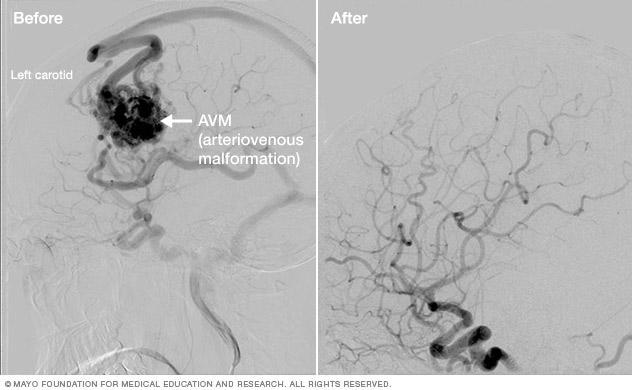

Brain arteriovenous malformation treatment results

Brain AVM before and after Gamma Knife treatment

Brain arteriovenous malformation (AVM) before Gamma Knife treatment (left) and 52 months after the procedure (right)

The treatment effect of stereotactic radiosurgery occurs gradually, depending on the condition being treated:

• Arteriovenous malformations (AVMs). The radiation therapy causes the abnormal blood vessels of brain AVMs to thicken and close off. This process may take two years or more.